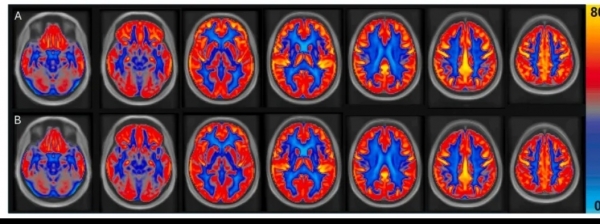

16周后,先进的脑部核磁共振成像(pCASL-MRI)揭示了令人惊喜的变化:

1. 大脑血流全面提升:食用花生后,参与者的全脑血流量平均增加了3.6%,而负责高级认知的灰质区域血流量提升更明显,达4.5%。形象地说,相当于为正在缓慢"缺水"的大脑田地,进行了一次有效的"灌溉升级"。

图:成人(n=31)在(A)花生干预和(B)无花生干预的平均脑血流量(CBF)图(论文截图)

2. 关键脑区获益显著:与记忆、语言处理密切相关的额叶和颞叶,血流量分别大幅增加了6.6% 和 4.9%。这为观察到的认知改善提供了坚实的生理基础。